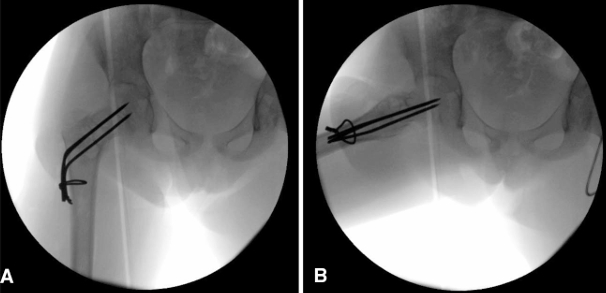

微信图片_2026-04-21_171948_353.png

微信图片_2026-04-21_171953_785.png

Follow-Up Results

During follow-up, growth-related migration of the K-wires toward the distal femoral neck was observed, slightly prolonging healing time.

This actually demonstrated one advantage of using smooth K-wires instead of screws, as they accommodate skeletal growth and reduce physeal injury risk.

1-Year Follow-Up

Radiographs showed progressive healing and remodeling.

2.5-Year Follow-Up

Complete bone union was achieved, and hardware removal was performed.

1 Year After Hardware Removal

The femoral neck remodeled to a normal neck-shaft angle.